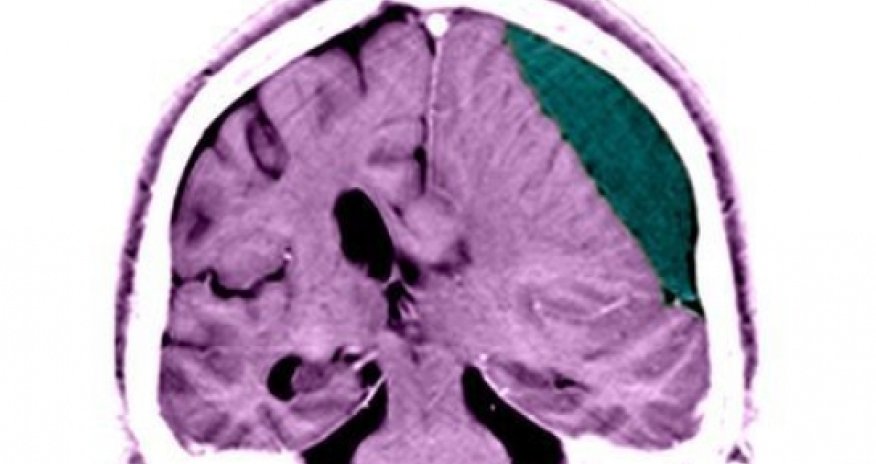

Injuries to the head can leave victims susceptible to early death even years later through impaired judgement, a major analysis of survivors shows.

Those with a history of psychiatric disorders before the injury are most at risk of dying prematurely.The study, in JAMA Psychiatry, of 40 years of data on more than two million people, showed that overall a brain injury trebled the risk.Suicide and fatal injuries were among the commonest causes of early death.More than one million people in Europe are taken to hospital with a traumatic brain injury each year.The study, by researchers at the University of Oxford and the Karolinska Institute in Stockholm, looked at Swedish medical records between 1969 and 2009.Treatable illnesses

They followed patients who survived the initial six-month danger period after injury.The data showed that without injury 0.2% of people were dying prematurely - before the age of 56.However, the premature-death rate was three-fold higher in patients who had previously suffered traumatic brain injury.In those who also had a psychiatric disorder the rate soared to 4%.Dr Seena Fazel, one of the researchers in Oxford, said: "There are these subgroups with really high rates, and these are potentially treatable illnesses, so this is something we can do something about."Judgement affectedCommon causes of premature death among those who had suffered previous brain injury included suicide, being a victim of assault or suffering fatal injuries, for example in a car crash.It is thought that the injury causes permanent damage to neural networks in the brain and can alter people's judgement and ability to deal with new situations.Prof Huw Williams, the co-director of the centre for clinical neuropsychology research at the University of Exeter, said: "The mortality rates are like a reverse-iceberg - they're the most awful outcome, but the rates of depression and anxiety are huge in the brain injury population."People with head injury need monitoring all the time in case they become suicidal."Dr Richard Greenwood, a consultant neurologist at Homerton Hospital in London, said post-mortem examinations showed 2% of people had evidence of brain injury, and his children were not allowed to play rugby because of the risk to the brain.(BBC)ANN.Az